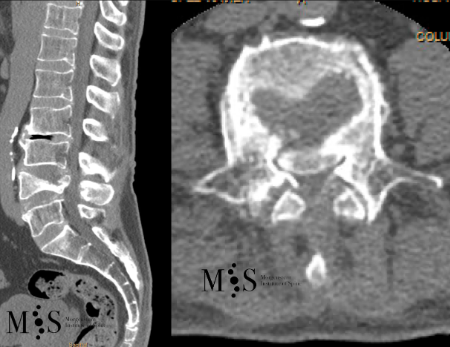

Example Clinical Case: Kyphoplasty

Pre- and post-operative comparison of a cemented kyphoplasty

Female, age 55, compression fracture of L2

Before 1

Before 2